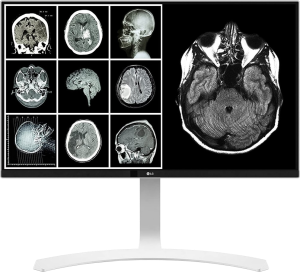

Kompaktne kirjeldav meditsiinimonitor on seade DICOM-standardile vastavate failide esitamiseks PACS-süsteemist, et tõlgendada meditsiinilisi kujutisi. Üldiselt on need diagnostilised monitorid, mis taasesitavad kõige täpsemal viisil igasuguste diagnostikaseadmete kujutiste üksikasju. Need on nii ühevärvilised kui ka värvilised meditsiinilised monitorid maatriksitega 1 MP kuni 5 MP, ühe või kahe monitori konfiguratsioonis ja 4 MP, 6 MP, 8 MP, 12 MP ühe paneeli konfiguratsioonis. Viimastel aastatel oleme näinud tugevat suundumust monokroomsete monitoride asendamisel värviliste monitoridega, mis võimaldavad kuvada pilte paljudest erinevatest viisidest, samuti traditsiooniliste kahe monitoriga jaamade asendamist ühe meditsiinilise monitoriga, millel on kõrge (ekvivalentne) eraldusvõime, mis tagab kõrgeim pildikvaliteet vastavalt DICOM standardile.

Üldradioloogia

Kirjeldav postitus:

- vähemalt 2 vertikaalselt töötavat monokroomset monitori,

- DICOM standardis,

- paarina ja tootja sidumistunnistusega

- minimaalne eraldusvõime: 1,92 megapikslit

- ekraani või pildi minimaalne töödiagonaal: 47,5 cm

- minimaalne heledus: 400 cd/m2

- minimaalne kontrastsus: 400/1

Tänu monitori lahutusvõimele ehk selle pildivälja pindalale on märgatavaks trendiks kahe monitoriga jaamades 3 MP monitoride kasutamine lubatud minimaalse 2 MP monitoride asemel. See trend kajastub ka (kombineeritud) ühe monitori jaamades, kus 4 MP monitoride asemel kasutatakse 6 MP monitore. Mõned kirjeldavate monitoride tootjad on juba selgesõnaliselt loobunud 2 MP ja 4 MP monitoride tootmisest.

Kuvatava pildi visualiseerimine monitoridel:

– 2 MP jäänud,

– 3 MP paremal